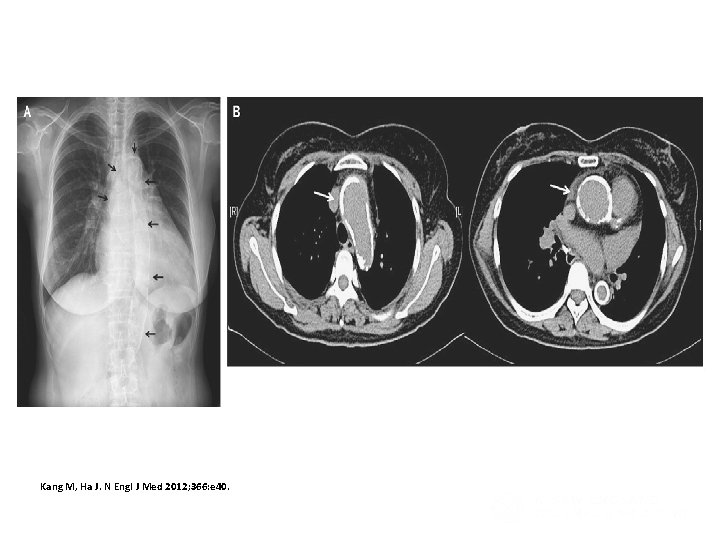

Porcelain Aorta Kang M, Ha J. N Engl J Med 2012; 366: e 40.

Blauth Cl, Cosgrove DM, Lytle BW, Loop FD Department of Thoracic and Cardiovascular Surgery, Cleveland Clinic Foundation, OH The Journal of Thoracic and Cardiovascular Surgery [1992, 103(6): 1104 -11; discussion 1111 -2] As the ages of patients undergoing cardiac operations have increased, noncardiac causes of death have increased. To identify these causes of death, we analyzed the autopsy findings in 221 patients undergoing myocardial revascularization or valve operations between 1982 and 1989. Mean age was 65. 6 +/- 9. 5 years and the range was from 32 to 94 years; 130 patients (58. 8%) were male. Autopsies were complete in 129 patients (58. 4%) and limited to the chest and abdomen in the remainder. Embolic disease was identified in 69 patients (31. 2%). Atheroemboli or abnormalities consistent with atheroemboli were identified in 48 patients (21. 7%). Fourteen patients had thromboembolism and 7 had disseminated intravascular coagulation. The prevalence of atheroembolic disease increased dramatically from 4. 5% in 1982 to 48. 3% in 1989 (p = 0. 001). Atheroembolic disease was found in the brain in 16. 3% of patients, spleen in 10. 9%, kidney in 10. 4%, and pancreas in 6. 8%. Thirty (62. 5%) of the 48 patients had multiple atheroembolic sites. Atheroemboli were more common in patients undergoing coronary artery procedures (43/165; 26. 1%) than in those undergoing valve procedures (5/56; 8. 9%) (p = 0. 008). There was a high correlation of atheroemboli with severe atherosclerosis of the ascending aorta. Atheroembolic events occurred in 46 of 123 patients (37. 4%) with severe disease of the ascending aorta but in only 2 of 98 patients (2%) without significant ascending aortic disease (p less than 0. 0001). Fortysix of 48 patients (95. 8%) who had evidence of atheroemboli had severe atherosclerosis of the ascending aorta. There was a direct correlation between age, severe atherosclerosis of the ascending aorta, and atheroemboli. Incremental risk factors for atheroembolic are peripheral vascular disease and severe atherosclerosis of the ascending aorta.